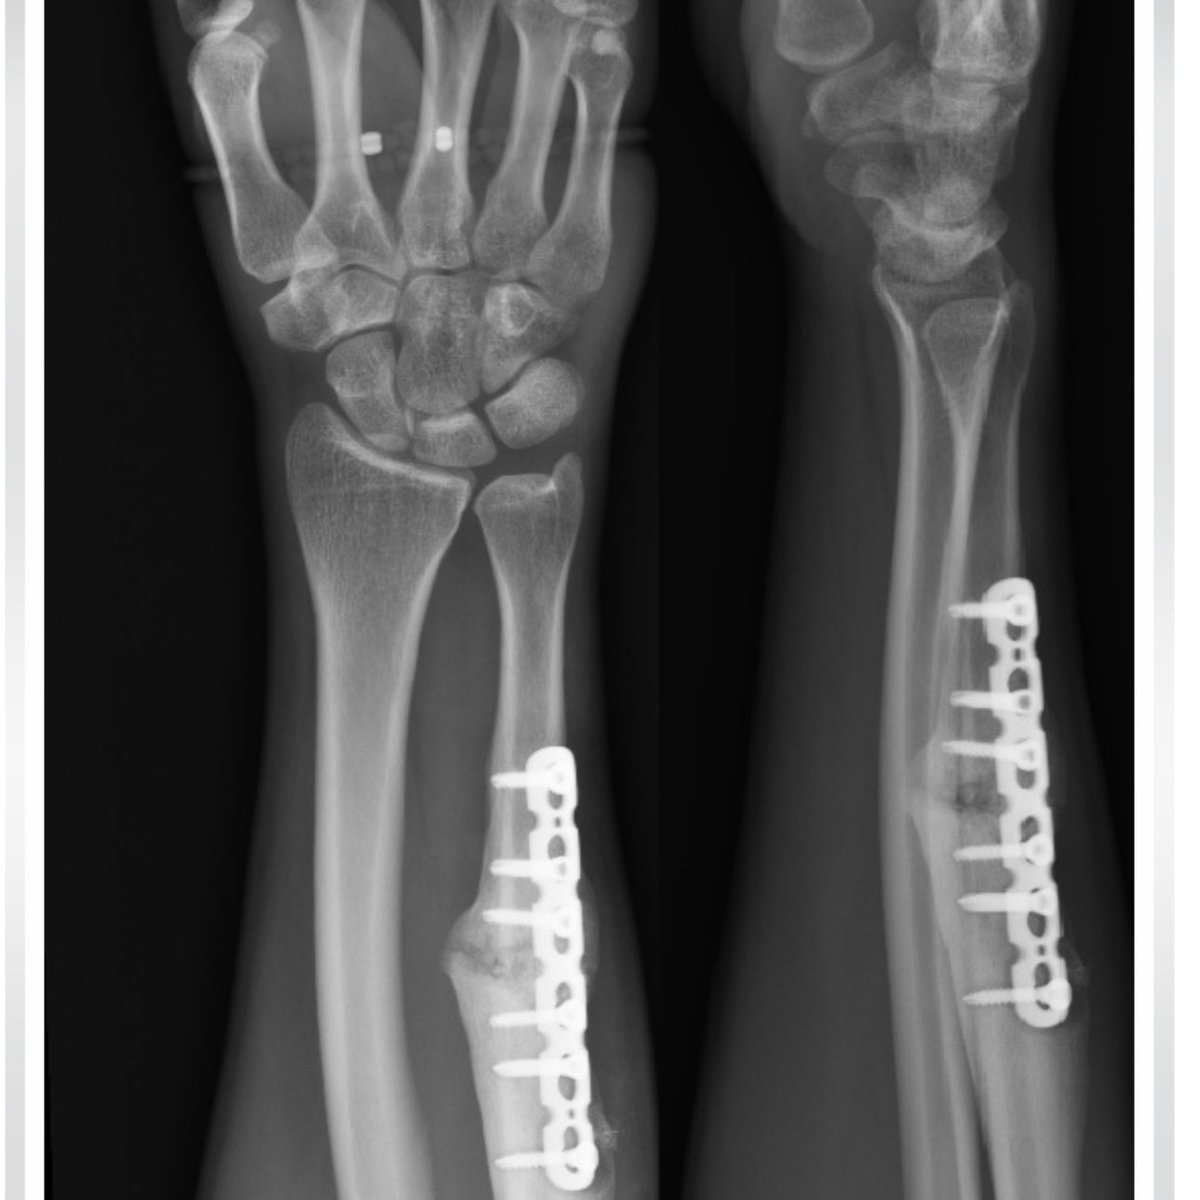

Delighted 35yr tennis player who had 2 x ACL ruptured + meniscus op consent ✅